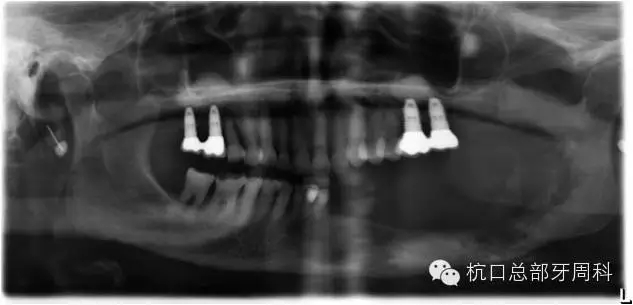

被診斷為種周炎時(shí)全景片  2011

111.webp.jpg